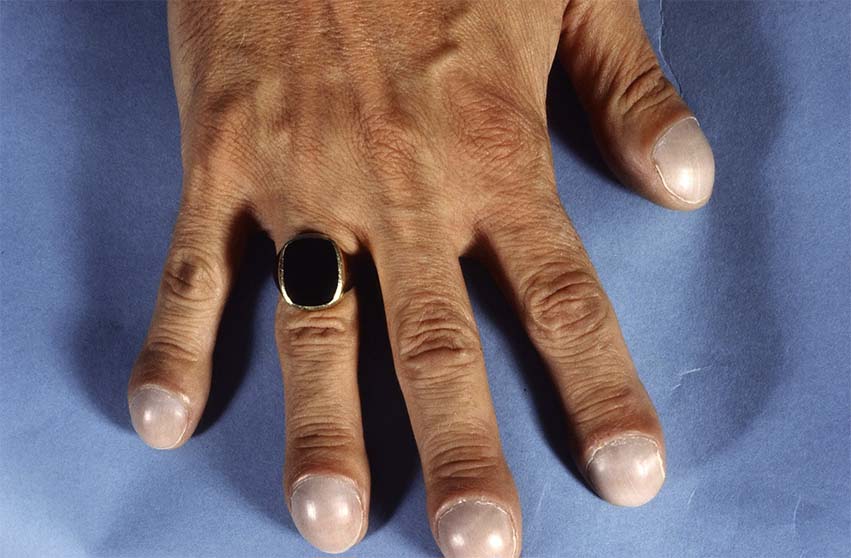

Een patiënt met deze afwijking heeft bolle nagels met bredere vingertoppen en geen nagelriemen. Je longen hebben een bijzondere anatomie en bevinden zich in je borstkas en worden omringd door je ribben. Dat wil zeggen dat we uit een verkleurde iris, of blauwgroene pus, of een bolle nagel, een hele wereld aan pathologie.

Enkele longaandoeningen, hartaandoeningen, huidaandoeningen en maagdarmaandoeningen gaan gepaard met dit symptoom. Mensen met hele bolle nagels, ook wel trommelstokvingers of horlogenagels genoemd, hebben nagels die over de vingertop heen groeien. Erg bleke of witte nagels ontstaan door ouder worden, maar het kan ook een teken zijn van serieuze aandoeningen, zoals bijvoorbeeld bloedarmoede, leverziekte, voedingsstoffentekort en hartfalen.

Trommelstokvingers of horlogeglasnagels zijn bolronde nagels en eindkootjes, welke worden geassocieerd met interne aandoeningen die gepaard gaan met onvoldoende doorbloeding (ischemie). But not sure were to start?. Normaalgezien is de afwijking niet pijnlijk, maar soms presenteert een patiënt zich met pijn in de vingertoppen.

Vormveranderingen (bolle, holle en kromme nagels) Trommelstokvingers (clubbed fingers), bolle nagels Bij trommelstokvingers zijn de nagels bolvormig, de hele eindkootjes zijn verdikt. Neem een kijkje op de beste bolle nagels longen in de foto’s hieronder en krijg ideeën voor uw fotografie!!!. De nagel drukt dan tegen de zijkant van de nagelwal.

Het is niet onverstandig om een afspraak te maken met uw huisarts wanneer u last heeft van bolle nagels. Bolle nagels ontstaan doordat u te weinig zuurstoftoevoer naar uw vingertoppen heeft. 4/mai/18 - Neem een kijkje op de beste bolle nagels longen in de foto’s hieronder en krijg ideeën voor uw fotografie!!!.

Kijkonderzoek in de longen (bronchoscopie) en biopsie U krijgt eerst plaatselijke verdoving met een spray of narcose. Bolle nagels komen vaak voor in combinatie met zogenaamde ‘ trommelstokvingers ‘. Hele bolle nagels van de vingers (trommelstokvingers).

Bij aandoeningen van het hart, de longen, grote bloedvaten of het maag-darmstelsel kan het zuurstofgehalte in het bloed afnemen. De vingertoppen zijn verdikt, warm en rood. De longen zorgen ervoor dat u iedere vier seconden die zuurstof krijgt.

Een 62-jarige man vertelt dat zijn nagels steeds boller worden en zijn vingertoppen steeds dikker. De arts schuift een buigzame slang met een kleine camera via uw mond of neus in de longen. Als dit niet op tijd verholpen wordt kan dit uitmonden in een ontsteking.

De vingertoppen zijn verdikt, warm en rood. Dat is meer dan .000 keer per dag of acht miljoen keer per jaar. Dan is het een aangeboren kenmerk.

Dunne bolle nagels Home//Forum//Handen & voeten//Dunne bolle nagels googletag.cmd.push(function() { googletag.display('div-gpt-ad-dokter_header');. Het ontstaat door een te laag zuurstofgehalte in je bloed, meestal veroorzaakt door long- of hartaandoeningen. Blush Pink Oval Nails Image source.

Bolle nagels komen voor als symptoom bij bepaalde longziekten en aandoeningen van het hart. That’s because of the flexibility they can give you in expressing your own idea. Als de nagels vooral wit zijn met donkere randen, dan kan dit wijzen op leverproblemen zoals hepatitis.